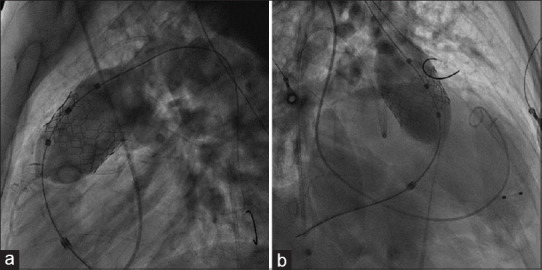

Transcatheter pulmonary valve implantation (TPVI) is the standard of care in patients with repaired tetralogy of Fallot (rTOF) presenting with right ventricular outflow tract (RVOT) dysfunction. However, the feasibility of TPVI is limited by the high cost and nonavailability of larger-sized valves for dilated native RVOT of rTOF patients. We report the first successful TPVI with a custom-made 35 mm balloon-expandable valve (Myval™) in a 30-year-old rTOF patient with severe pulmonary regurgitation and RV dysfunction.

Abstract Image